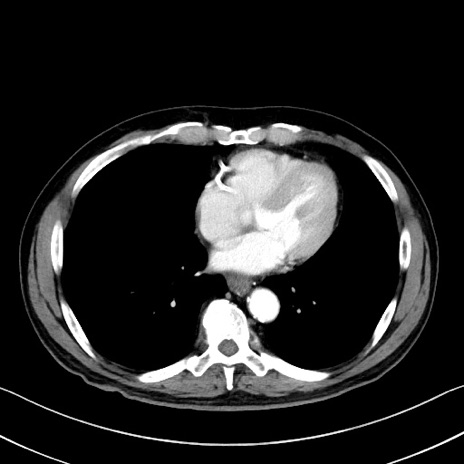

冠状断像

【症例】70歳代 男性

【主訴】腹部膨満、嘔吐

【現病歴】昨日より腹部膨満感出現。本日増悪し、仙痛出現。嘔吐あり、受診。

【既往歴】糖尿病、胆摘後

【身体所見】BP 149/80mmHg、HR 74/min、BT 35.9℃、腹部:膨満、軟、圧痛なし。腸雑音減弱あり。上腹部正中切開瘢痕あり。

【データ】WBC 13500、CRP 1.72